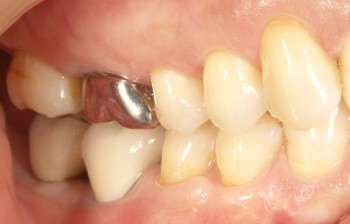

インプラントの術前・術後 Kさん